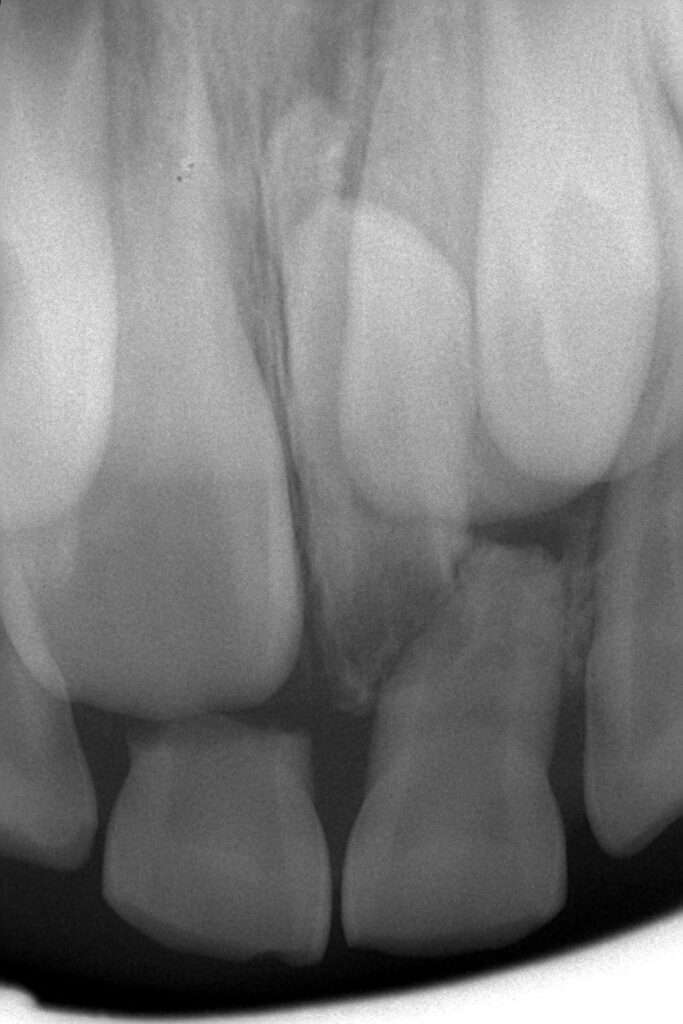

一般的な視覚的診査に加え専用機器を用いた診査を行い、より科学的根拠に基づいた診断のもと治療を行います。早期発見、早期治療を行うことにより、治療回数を減らすこと、歯の神経を取らずにダメージを最小限に抑えることができます。

当院ではレントゲンの結果や口腔内カメラの使用により患者様の歯の健康状態や治療方針を丁寧にカウンセリングし、十分理解していただいた上で治療しております。